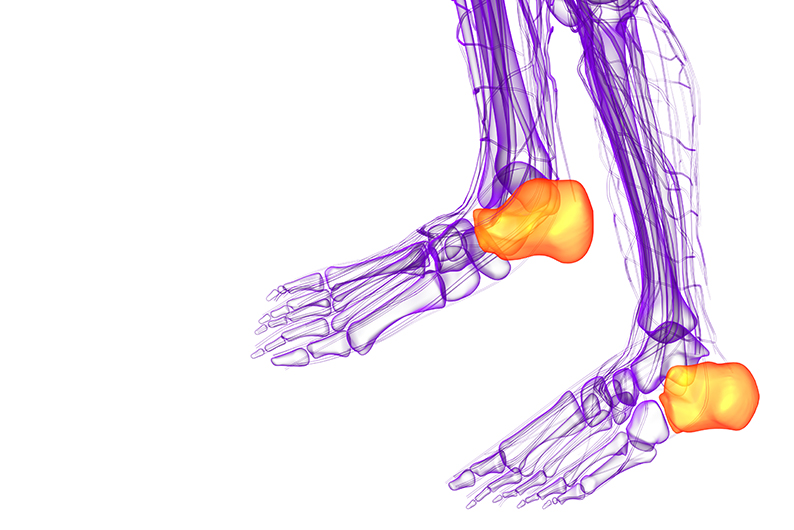

족저근막은 발바닥의 두꺼운 섬유질 막으로 발의 아치를 형성하고 걸을 때 발을 강력하게 지지해줍니다. 걸으면서 발뒤꿈치를 올리면 발뒤꿈치의 족저근막 부착 부위에 높은 장력이 가해집니다.

특히 달리기와 같은 활동 중에는 더 높은 장력이 가해져서 족저근막 부착 손상의 위험이 증가하게 됩니다. 족저근막염은 가벼운 부상이나 과도한 사용으로 인한 염증으로 발뒤꿈치와 발바닥에 통증을 일으키는 질환입니다. 아침에 일어나서 방바닥에 발을 딛는 순간 통증으로 깜짝 놀라는 경험을 해보신 적이 있다면 족저근막염 증상을 의심해봐야 합니다.

통증은 일반적으로 발뒤꿈치 안쪽과 바닥에서 느껴집니다.